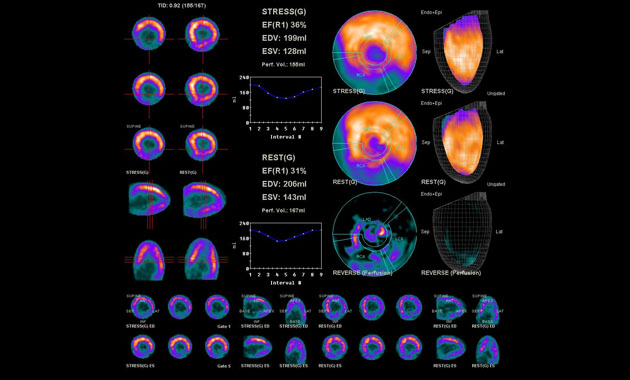

- Experience in comprehensive multi-modality imaging of cancer and advanced nuclear cardiology imaging studies

- Cardiac PET Imaging